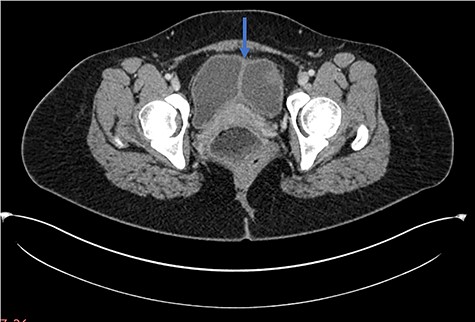

A 28-year-old woman presented to the emergency department with a 1-week history of abdominal pain, bloating and constipation. A computed tomography (CT) scan was performed, which demonstrated distension and a lead pipe appearance of the right colon suggesting a mild colitis (Fig. 1). The CT scan also demonstrated a duplicated segment of colon with a blind ending proximal limb (Figs 1 and 2), uterine didelphys (Fig. 2) and a duplicated bladder (Fig. 3). A subsequent magnetic resonance imaging scan demonstrated an 11 cm segment of thickened bowel with mucosal ulceration and surrounding hyperaemia confined to the duplicated colon. Sigmoidoscopy was performed and histology from the duplicated descending colon demonstrated mild active chronic colitis with crypt inflammation and associated abscesses without granuloma formation. The native colon had an unremarkable appearance. The patient was started on mesalazine and has had no further complaints of abdominal pain or bloating.

Axial CT scan demonstrating longitudinal sagittal septum giving rise to a duplicated bladder appearance.